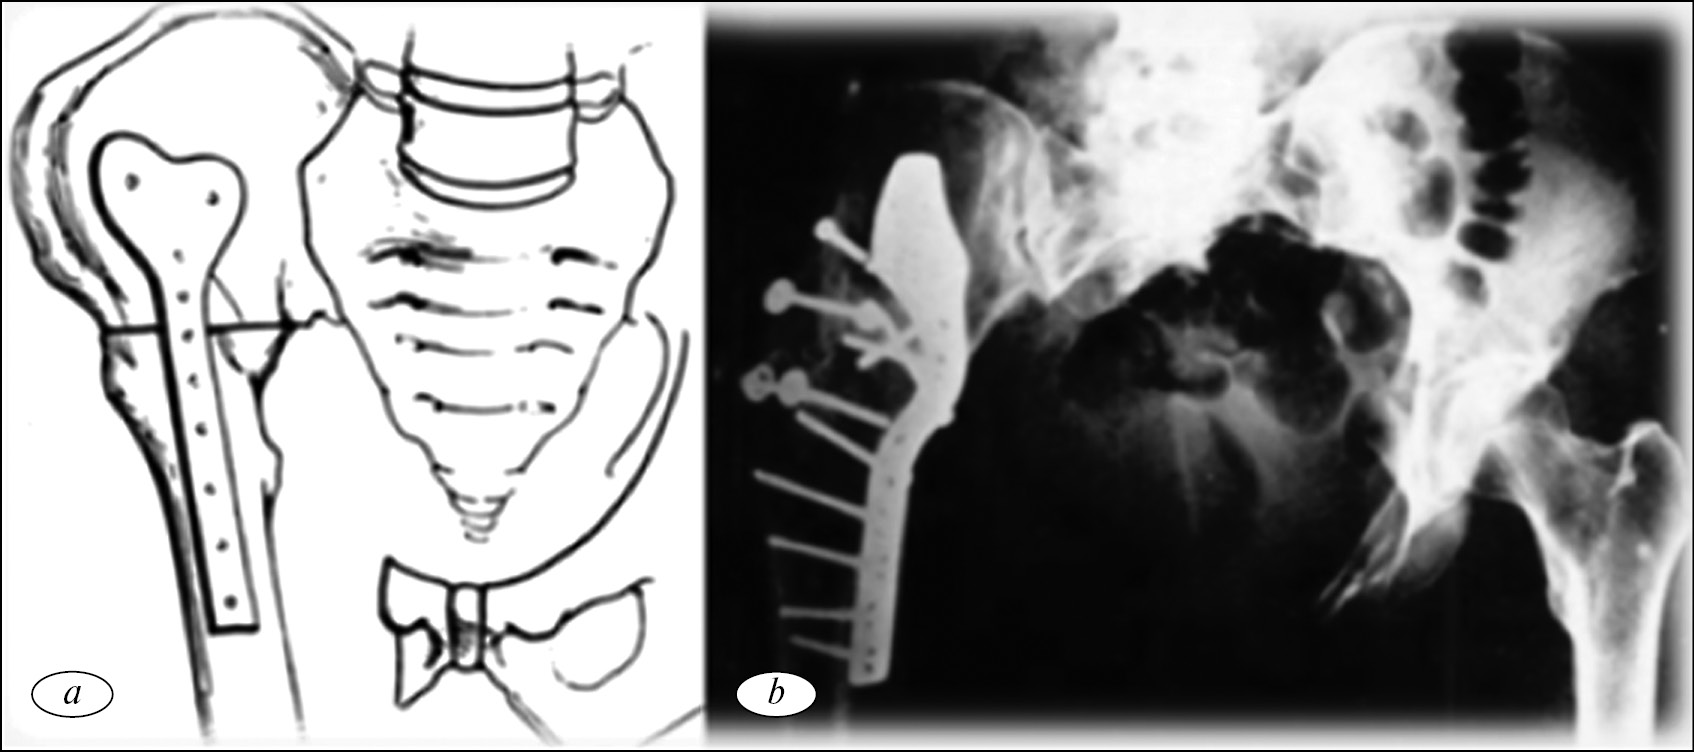

Реконструкция при помощи артродеза

Альтернативная методика реконструкции вертлужной впадины была предложена M.I. O’Connor и F. Sim в 1989 г. [19]. Опороспособность конечности после удаления опухоли восстанавливалась путем формирования различных типов артродеза проксимального отдела бедренной кости с подвздошной и лонной костями при помощи металло-остеосинтеза (рис. 2).

Рис. 2. Реконструкция вертлужной впадины при помощи артродеза проксимального отдела бедренной кости с подвздошной костью: a — cхема операции; b — рентгенограмма костей таза с подвздошно-бедренным накостным металлоостеосинтезом пластиной и артродезированием [19]

Авторы сообщает о 29 прооперированных больных с саркомами костей параацетабулярной области. Средний период наблюдения составил 66 мес. Прогрессирование заболевания диагностировано у 12 (40 %) прооперированных больных, при этом рецидив опухоли отмечен лишь у 2 (8 %) пациентов. Функциональный результат после операции оценен как хороший у 35 %, удовлетворительный у 25 % и неудовлетворительный у 40 % больных. Общее количество осложнений составило 62 %. Инфицирование послеоперационной раны было у 31 % и формирование ложного сустава области артродеза также у 31 % пациентов [19].